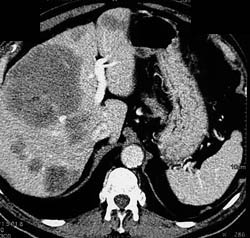

Focal Nodular Hyperplasia (FNH)